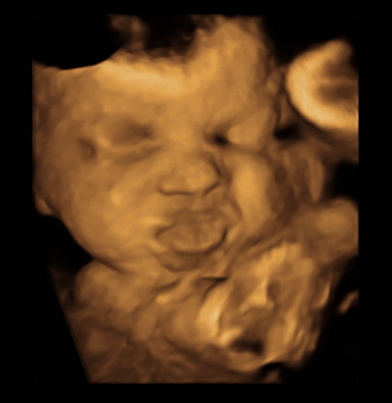

Just got back from my weekly ultrasound and 2 week doctor appointment. Everything still looks great for the both of us. She even flipped back head down from last week. We got some cute shots of her. Here are a few: (I love the one of her sticking her tongue out)

Had a 32 week ultrasound today to check the distance of my placenta to my cervix because it was too close at my 20 week scan. But, thank goodness, as my uterus stretched, my placenta moved up so I'm safe from a scheduled c-section! Woohoo! Also, everything else with baby looked good. He's head down, which means I've been rubbing and talking to his BUTT for the past couple weeks. Best part was the tech got us a couple 3D pics which we didn't expect. He definitely has daddy's flat bridge nose. him.